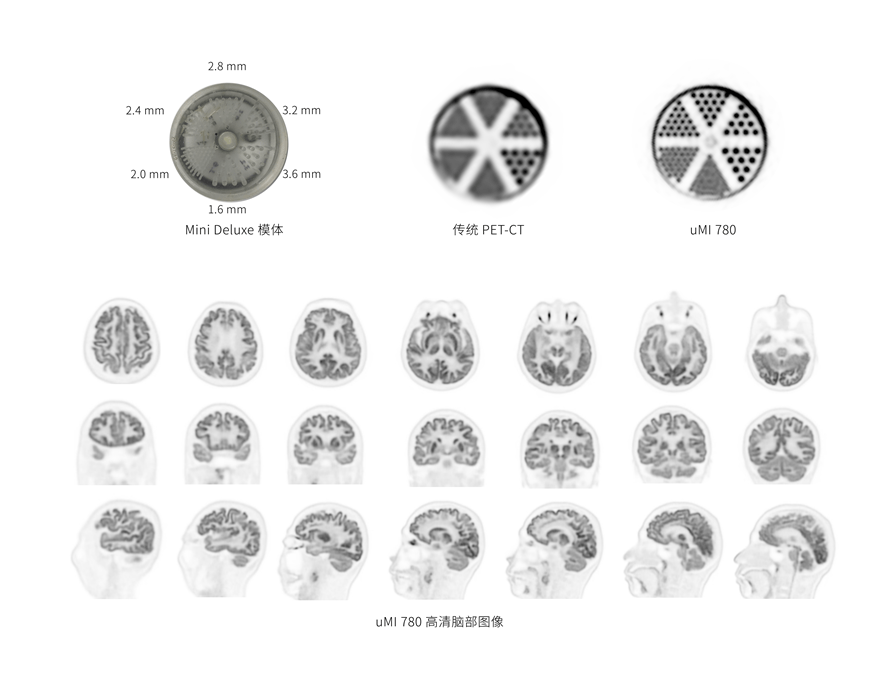

超清显像

2.9mm

超清NEMA分辨率成像

TOF + PSF

微小病灶无以遁形

600 x 600

超大矩阵,高精度超清重建